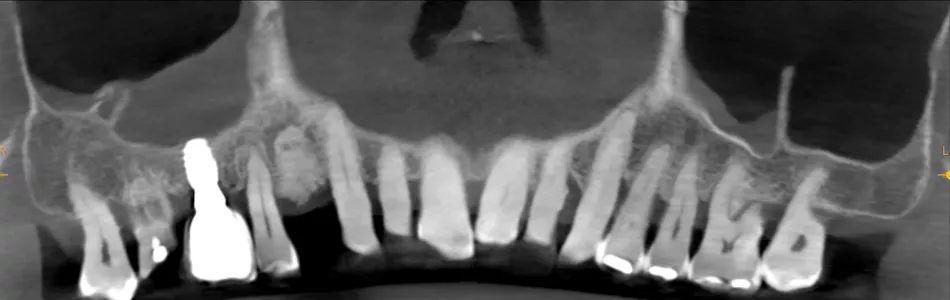

A 78-year-old male in good general health, with no medication and a negative smoking history, presented with mobility of the maxillary right second premolar (tooth 15) (Fig 1a. 1b). Clinical examination revealed severe occlusal wear, plaque accumulation, subgingival calculus, bleeding on probing, and multiple carious lesions. Periodontal assessment showed probing depths >10 mm and grade III mobility. CBCT confirmed circumferential vertical bone loss around tooth 15 and generalized periodontal involvement, indicating a hopeless prognosis and the need for extraction (Fig 1c).

1a. 1b. 1c. CBCT and panoramic views showing severe bone loss around tooth 15, confirming hopeless prognosis.

1c